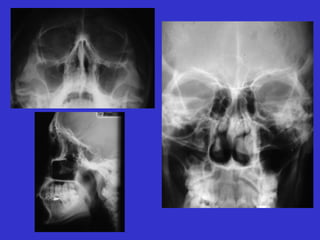

Este documento describe las diferentes proyecciones radiográficas utilizadas para examinar los senos paranasales, incluyendo las proyecciones básicas de Caldwell, Waters lateral y las proyecciones especiales como Hirtz y Waters mentonasal. También describe las diferentes estructuras anatómicas que componen el complejo ostiomeatal anterior y posterior de los senos paranasales.